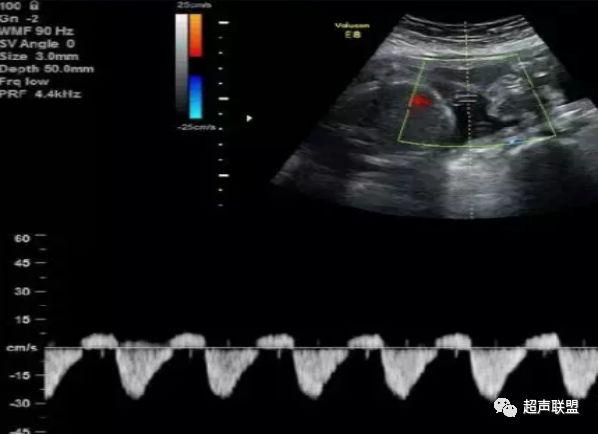

3 胎儿静脉导管

当右心负荷增大,心功能失代偿时,静脉回流受阻,静脉导管a波收缩期流速下降,血流消失甚至倒置。

5、静脉导管:a波消失或反向(见于严重的胎儿宫内缺氧);

3、静脉导管a波反向或消失;

图5 胎儿宫内正常静脉导管

图6 胎儿宫内缺氧时静脉导管a波反向